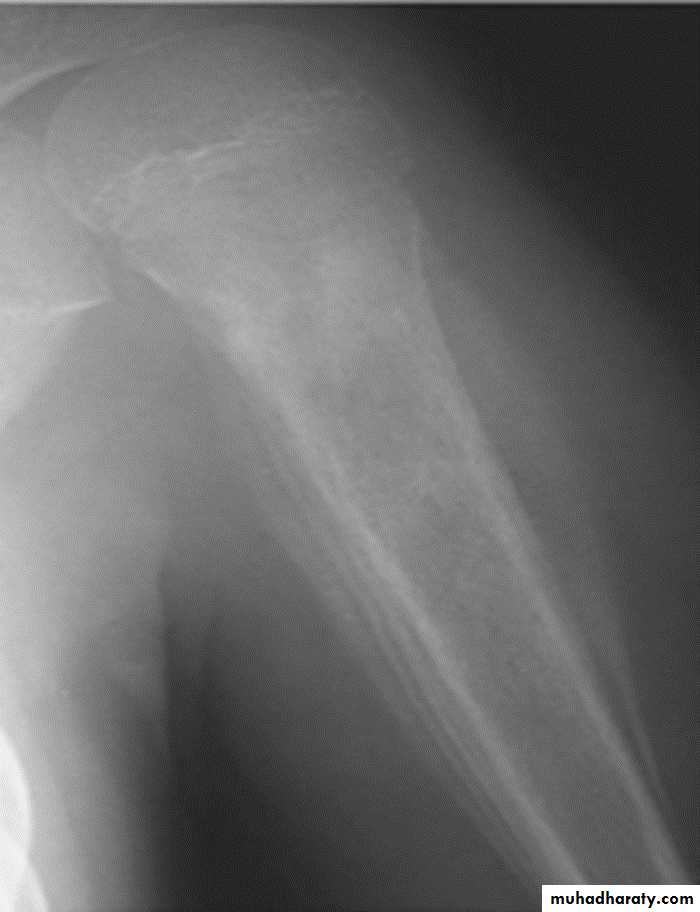

Osteo sarcoma is the commonest primary malignant bone tumor in young adults,

Area of bone destruction or sclerosis with ill-defined margins, wide zone of transition & periosteal reaction with or without cortical destruction & soft tissue swelling.Osteosarcoma :

Age: 5-20-yrs, elderly with Paget's disease.Site: metaphyseal around the knee joint.

Findings:

Lytic

Blastic

Mixed

Poorly defined bony destruction.

Sun ray speculation (periosteal reaction).

Elevation of the periosteum at the margin producing the so called Codman's triangle.

Cortical destruction.

Soft tissue swelling.